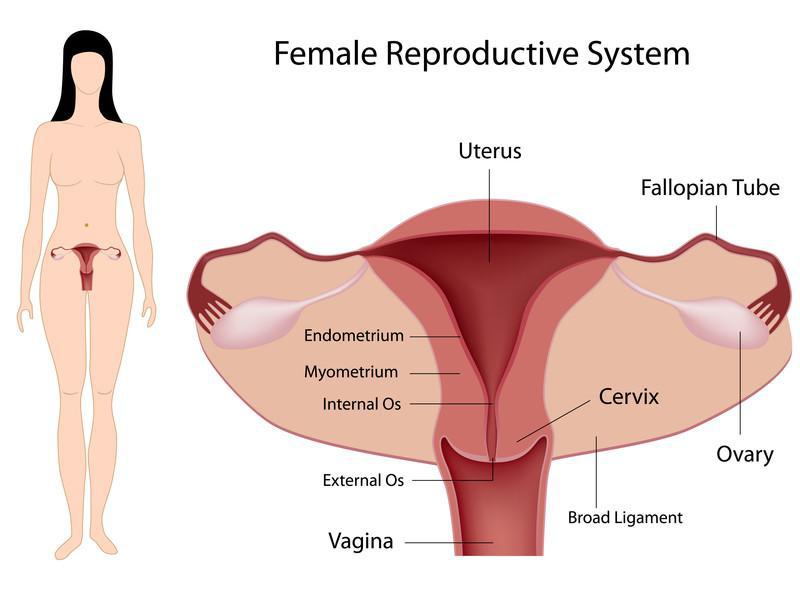

Having a baby of your own takes just two steps.

Healthy sperm and an egg.

And the right ‘womb preference’ for the fertilized egg to form, grow, and mature for birth.

Pregnancy first starts with sperm cells and an egg.

Eggs live in ovaries, and the hormones that control your menstrual cycle cause a few eggs to mature every month.

These hormones also make the lining of your uterus thick and spongy, which gets your body ready for pregnancy.

During this process, any obstruction from your womb would either render your egg immovable or the sperm dead.

Infertility occurs primarily from the combination of fibroids, ovarian cysts, tubal blockage, and sometimes a hot stomach.

First, the healthy spermatozoa need to fight their way through your body to your egg.

If, by chance, they get in, they’ll struggle with fibroids to gain space to grow.

They’ll also face the womb conditions to get through, and all this would only be possible if the fallopian tubes are open.